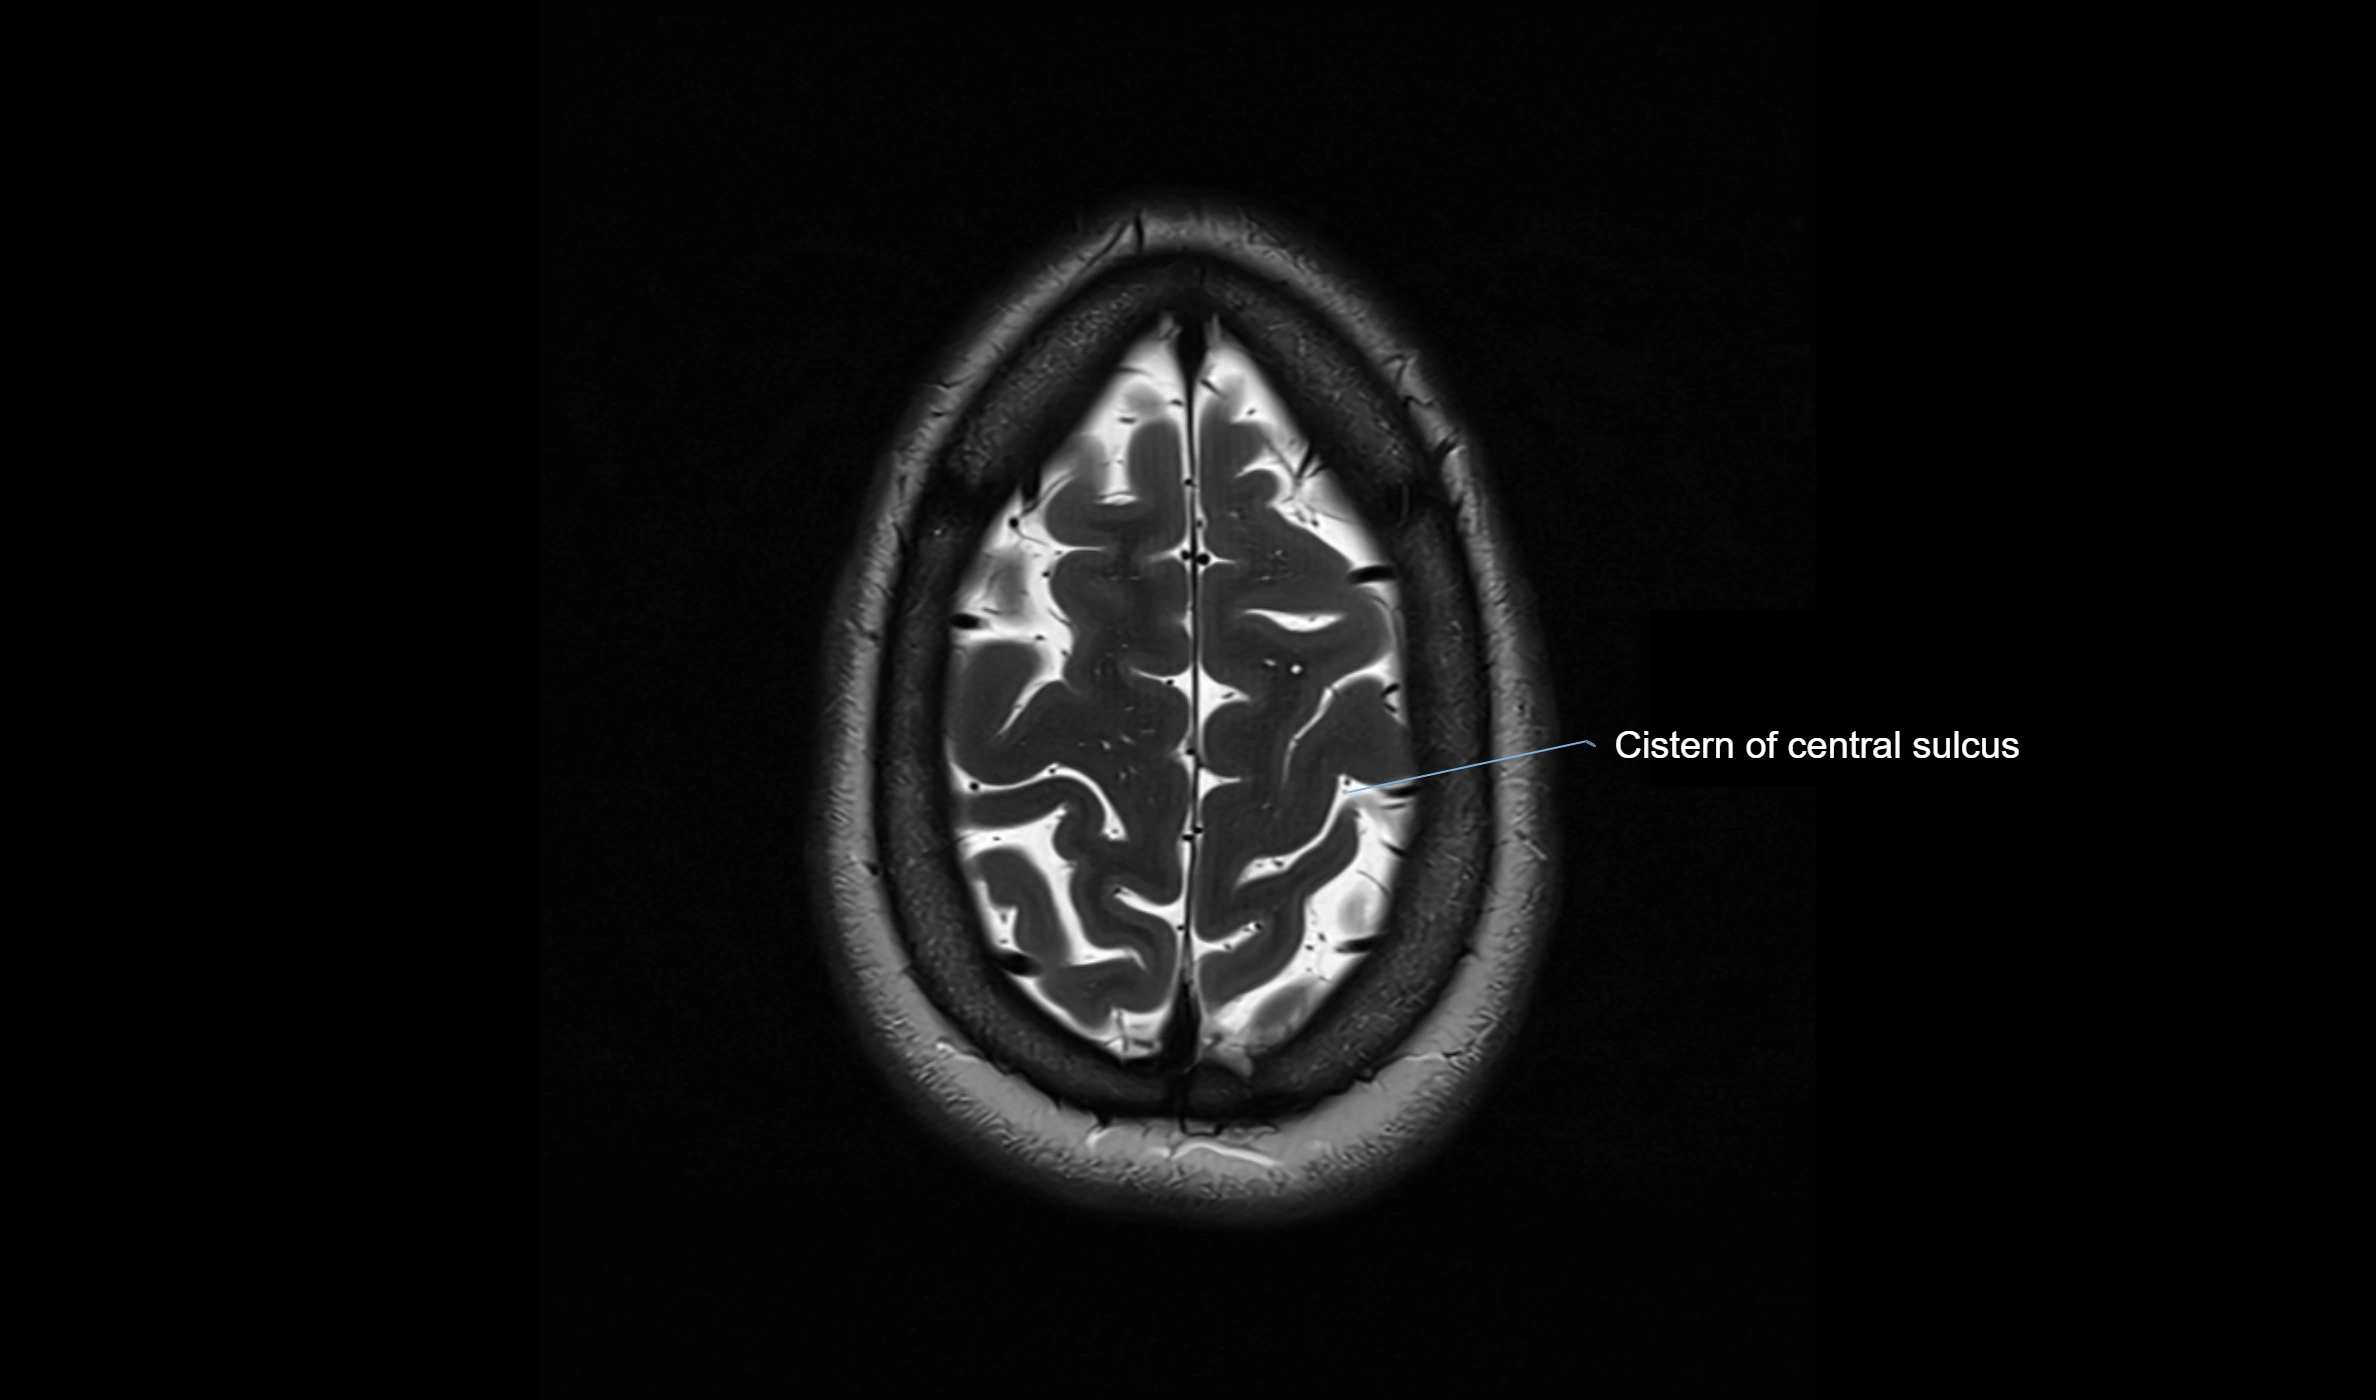

MRI Appearance

• T2-weighted images:

• The cistern is hyperintense (bright) due to the high water content of CSF.

• Encapsulated vessels and nerves are seen as flow voids or hypointense lines within the bright background.